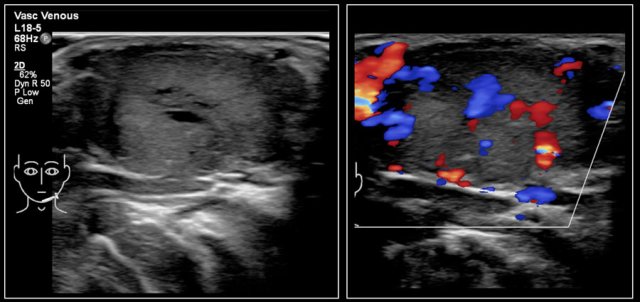

Here an image of a 16-year-old girl with hyperthreoidism.

A diffusely enlarged thyroid gland is seen with hyperemia.

The final diagnosis was Graves disease.

In Graves disease the thyroid gland is also enlarged and shows an increased perfusion.

On color Doppler it has been described as an inferno in red and blue.